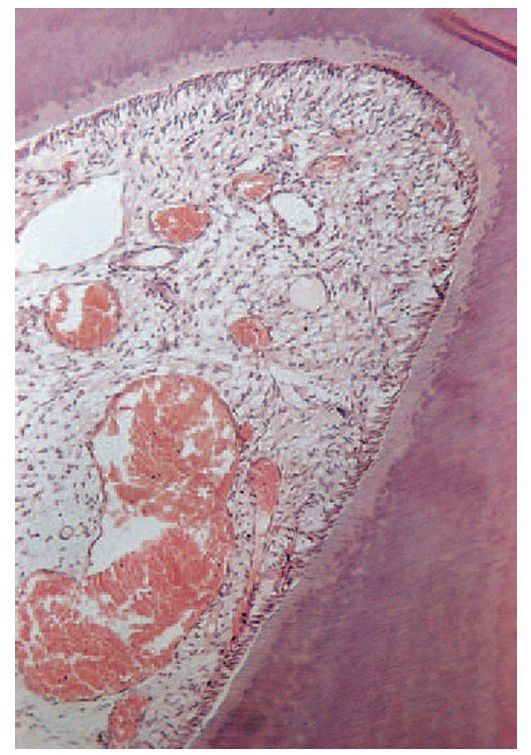

Pulpal hyperaemia.

While bacteria are still some distance from the pulp, acid permeating along the dentinal tubules gives rise to hyperaemia, oedema and a light cellular infl ammatory infi ltrate in the pulp.